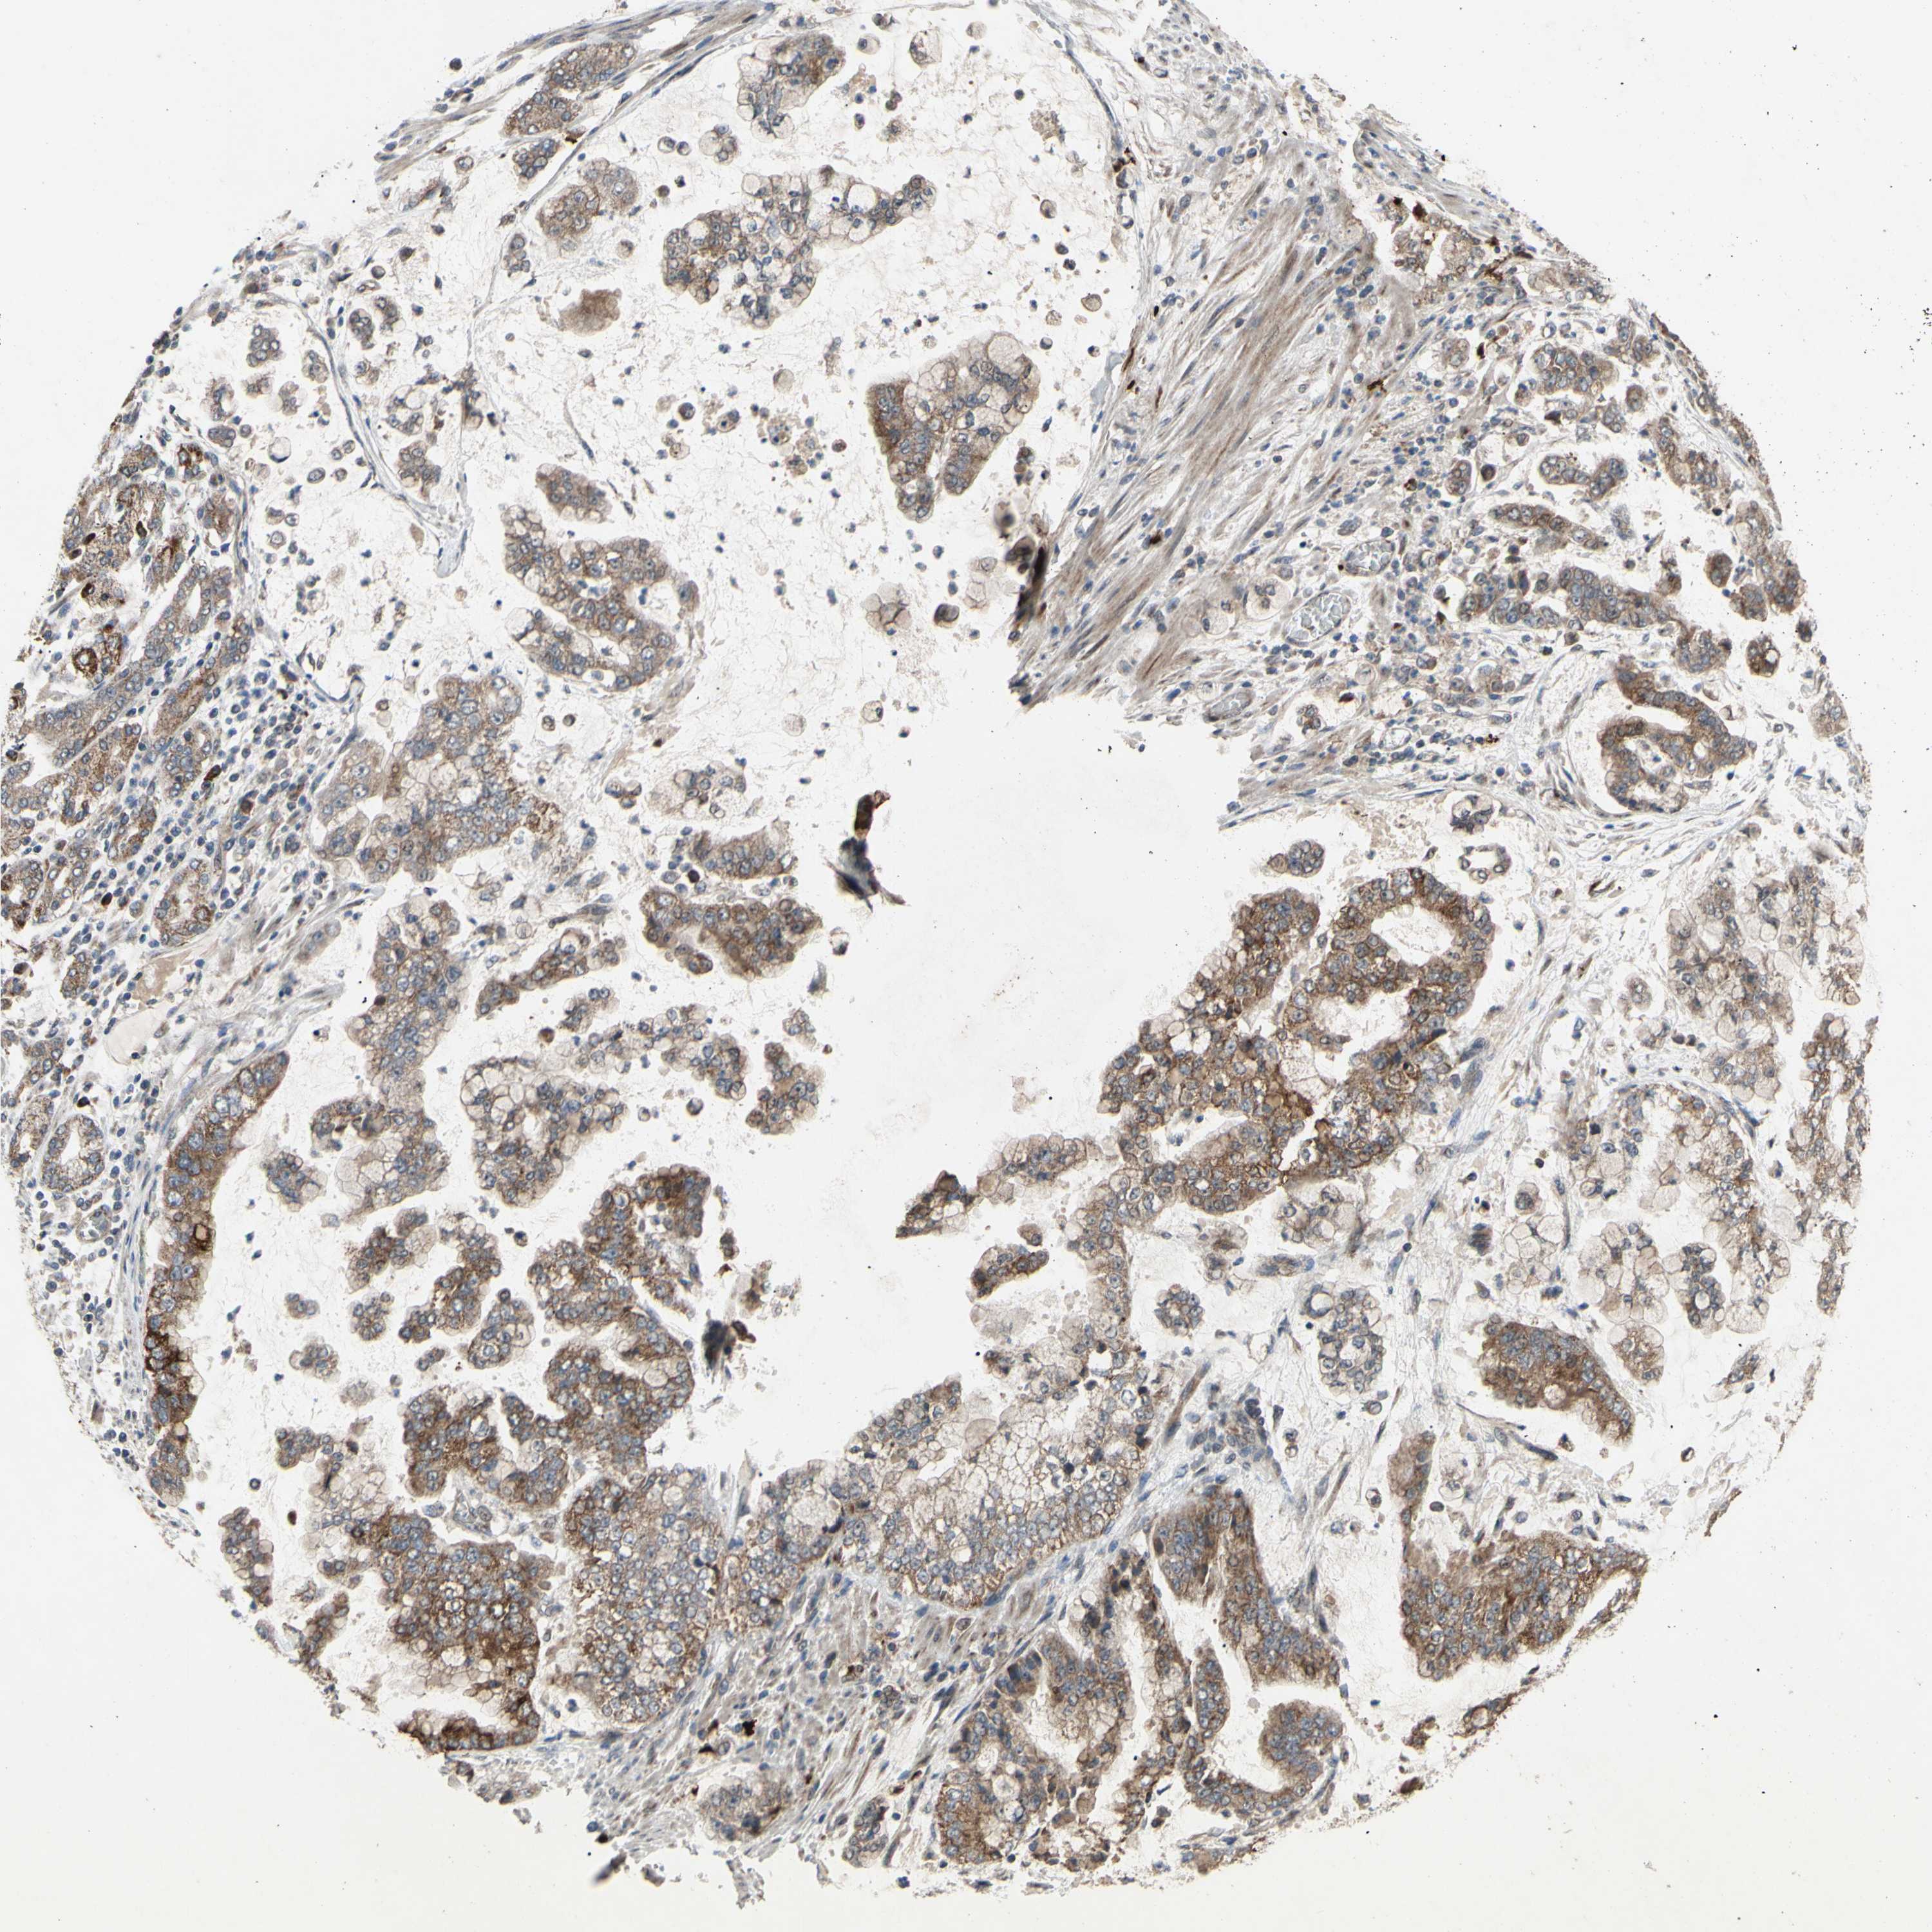

STOMACH CANCER - Protein expressioni

A mouse-over function shows sample information and annotation data. Click on an image to view it in a full screen mode. Samples can be filtered based on level of antibody staining by selecting one or several of the following categories: high, medium, low and not detected. The assay and annotation is described here.

Note that samples used for immunohistochemistry by the Human Protein Atlas do not correspond to samples in the TCGA dataset.

Antibody stainingi

Antibody staining in the annotated cell types in the current human tissue is reported as not detected, low, medium, or high, based on conventional immunohistochemistry profiling in selected tissues. This score is based on the combination of the staining intensity and fraction of stained cells.

Each image is clickable and will lead to virtual microscopy that enables deeper exploration of all samples and also displays staining intensity scores, fraction scores and subcellular localization as well as patient and tissue information for each sample.

Antibody HPA010636

Staining

High

Medium

Low

Not detected

Intensity

Strong

Moderate

Weak

Negative

Quantity

>75%

75%-25%

<25%

None

Location

Nuclear

Cytoplasmic/membranous

Cytoplasmic/membranous,nuclear

Adenocarcinoma, NOS

Adenocarcinoma, High grade